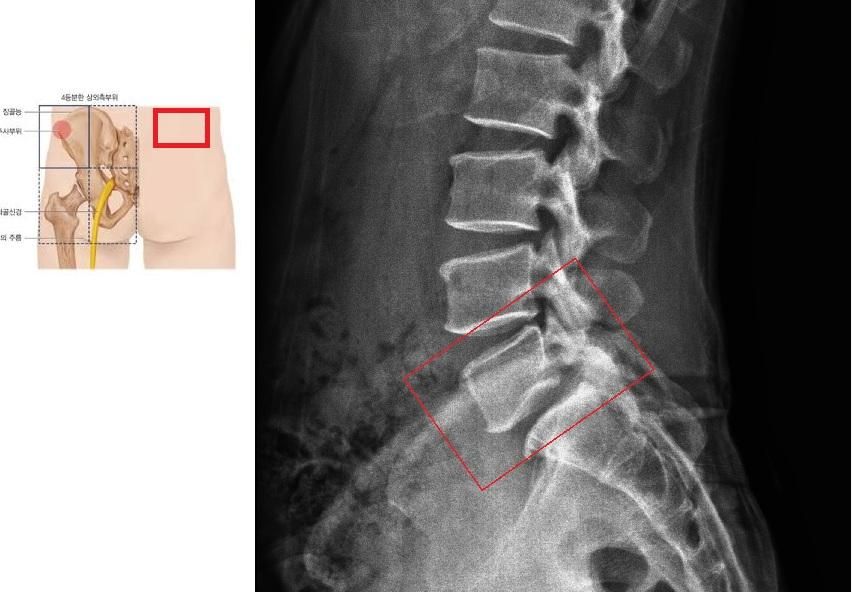

통증 발생 후 현재까지 10일 가량 계단/언덕 오르기 운동을 멈추고 진통제를 먹어도 나아지는 게 없어 정형외과에서 진료를 받았는데 x레이를 찍어보니 S1과 L5 사이에 협착 의심 소견 (x레이 사진) 외에 별 다른 말은 없었습니다.

• 1번 째 사진

• 설명하신 통증 양상과 위치(허리 아래, 엉덩이 위쪽 한쪽) 그리고 “허리를 세우면 바로 사라지고, 쪼그려 앉거나 허리가 말리는 자세에서만 아픈 점”을 보면 전형적인 신경 압박성 통증보다는 후관절(관절성 통증) 또는 천장관절, 혹은 주변 근막·근육 문제 가능성이 더 높습니다. 단순 X-ray에서 보이는 L5-S1 협착 의심 소견은 연령대에서 흔히 보이는 변화이고, 현재 증상과 반드시 일치한다고 보기는 어렵습니다.

또는 요추의 후관절 증후군일 수도 있고 허리를 구부리거나 말면 통증이 발생하고 특정 자세에서만 아프고 자세를 바꾸면 사라지고 엑스레이에서 L5~S1 협착 소견을 들으셨다면 해당 질환을 의심해볼 수 있습니다.